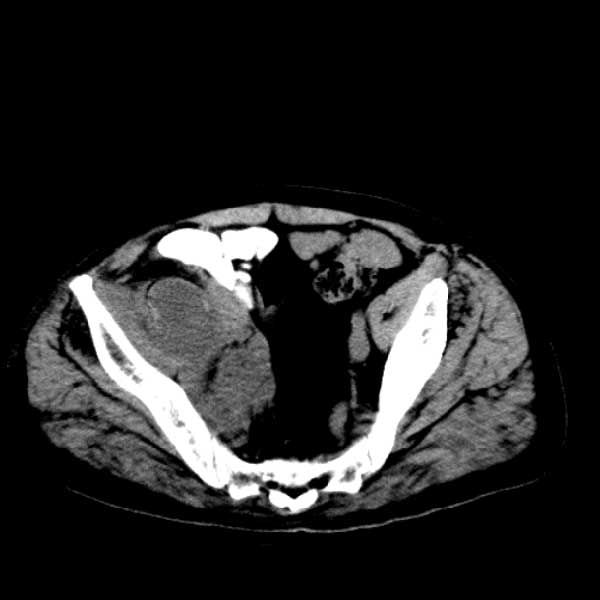

标题: CT13513:男 71 腹部疼痛20余天,近几天高热就诊,骨窗未见异 [打印本页]

标题: CT13513:男 71 腹部疼痛20余天,近几天高热就诊,骨窗未见异

考虑右侧腰大肌脓肿,向右髂窝、右腹股沟流注。

支持化脓性阑尾炎伴右髂窝脓肿、腰大肌腰方肌脓肿形成。

考虑腹腔及盆腔化脓性炎症,累及右侧髋关节及腹股沟区.

首先考虑化脓性阑尾炎伴腰大肌、腰方肌脓肿,不除外回盲部结核。

回盲部癌待排除。

患者肠镜检查考虑结肠癌,病理证实

患者肠镜检查考虑结肠癌,病理证实。肺部ct可见多发结节,考虑转移